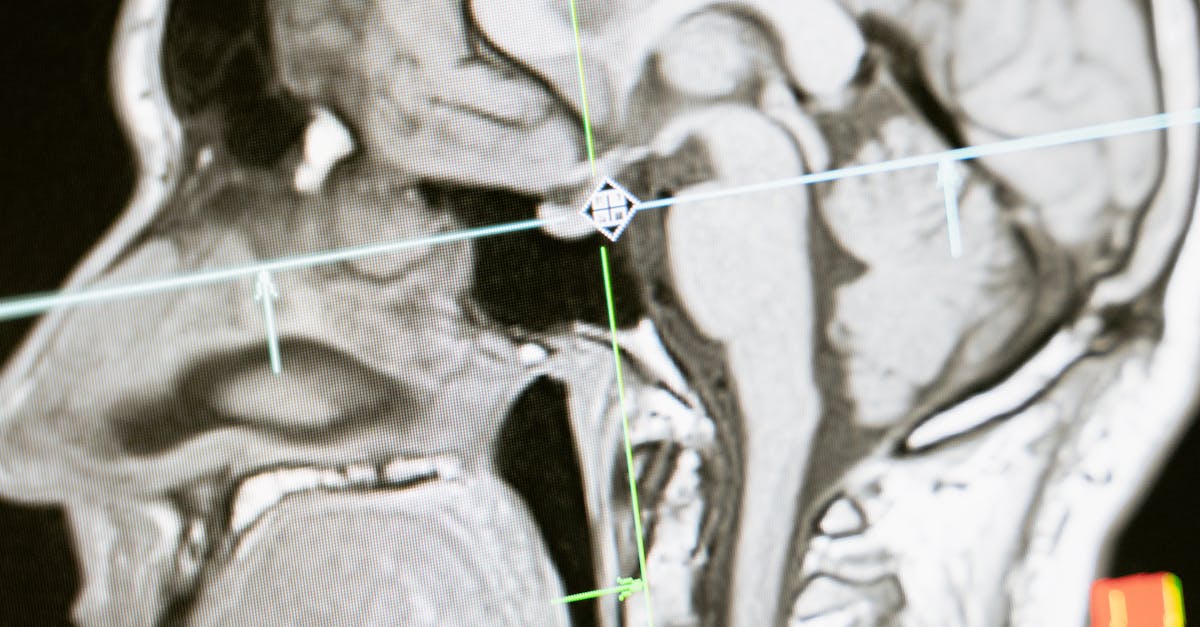

La décompression neurovertébrale consiste à appliquer une traction douce sur la colonne vertébrale. Ce processus vise à créer de l’espace entre les vertèbres. En faisant cela, on réduit la pression sur les disques intervertébraux et sur les nerfs adjacents. Ce soulagement permet d’améliorer la circulation sanguine au niveau des zones impactées.

La décompression neurovertébrale est une technique qui consiste à appliquer des tractions douces sur la colonne vertébrale. Cette méthode a pour objectif de créer un espace entre les vertèbres, ce qui diminue la pression sur les disques intervertébraux et les nerfs adjacents. En favorisant une circulation sanguine optimale autour des zones touchées, la décompression neurovertébrale permet d’atténuer les douleurs neuropathiques et d’améliorer le processus de guérison des tissus endommagés.

La décompression neurovertébrale consiste à appliquer des tractions contrôlées sur la colonne vertébrale. Ce processus permet de créer un espace entre les vertèbres, ce qui réduit la pression exercée sur les disques intervertébraux et les nerfs environnants. En diminuant cette pression, la méthode favorise une circulation sanguine améliorée, essentiel pour la régénération des tissus et le soulagement des douleurs. Les résultats de cette technique indiquent qu’elle peut être particulièrement efficace pour les seniors souffrant de douleurs neuropathiques liées à des problèmes discaux, tel que les hernies discales ou la sténose spinale.